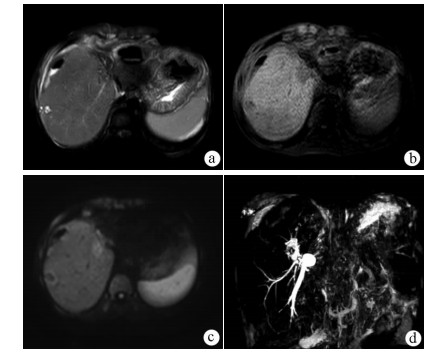

Intraductal papillary neoplasm of the bile duct with atrophy of the hepatic left lateral lobe: A case report

Jingzhong OUYANG, Ruili ZHU, Yanzhao ZHOU, Zhengzheng WANG, Xun CHEN, Jinxue ZHOU, Qingjun LI

2021, 37(7): 1676-1678. DOI: 10.3969/j.issn.1001-5256.2021.07.041

Abstract(964) HTML (382) PDF (2403KB)(58)